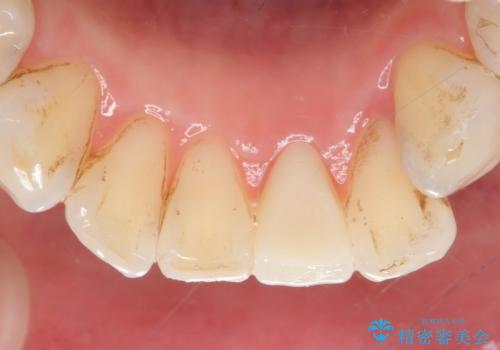

- 下顎前歯が茶色いのが気になるのでセラミックで治療したいといらっしゃった方の症例です。

再根管治療後、オールセラミッククラウン(スペシャル)による補綴を行いました。